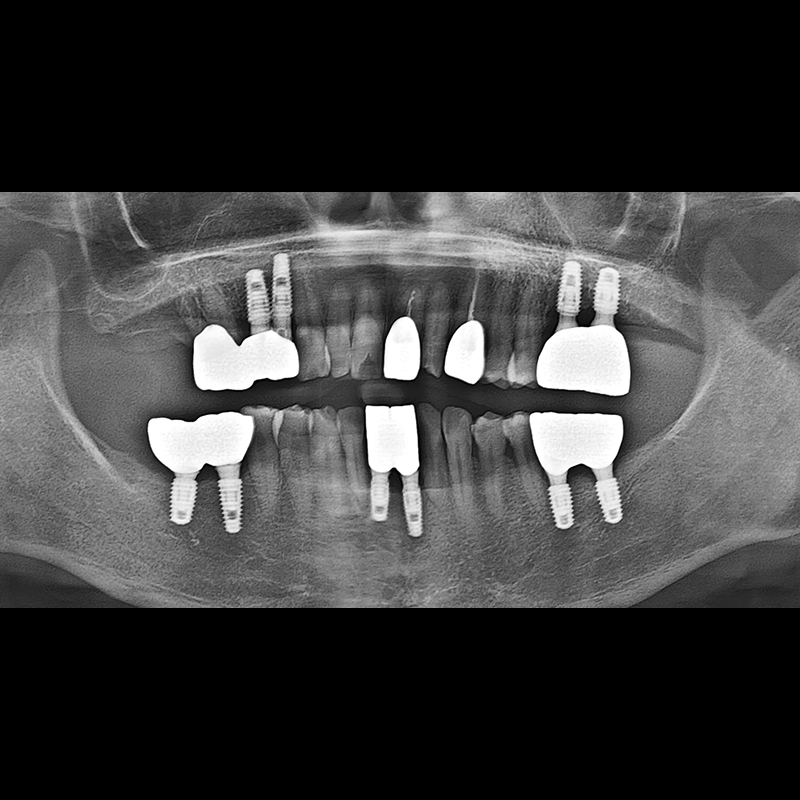

BEFORE AFTER

种植牙前后的照片 2025.05.30

在缺失的牙齿部分和难以挽救的牙齿位置植入了种植牙。